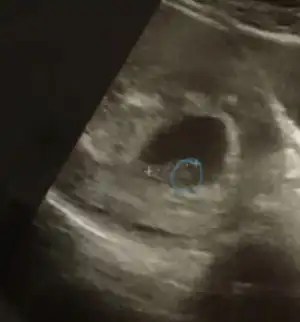

Benimde 6 7 haftalıkken kese görüntüsü tahmin edermisiniz cinsiyetini?